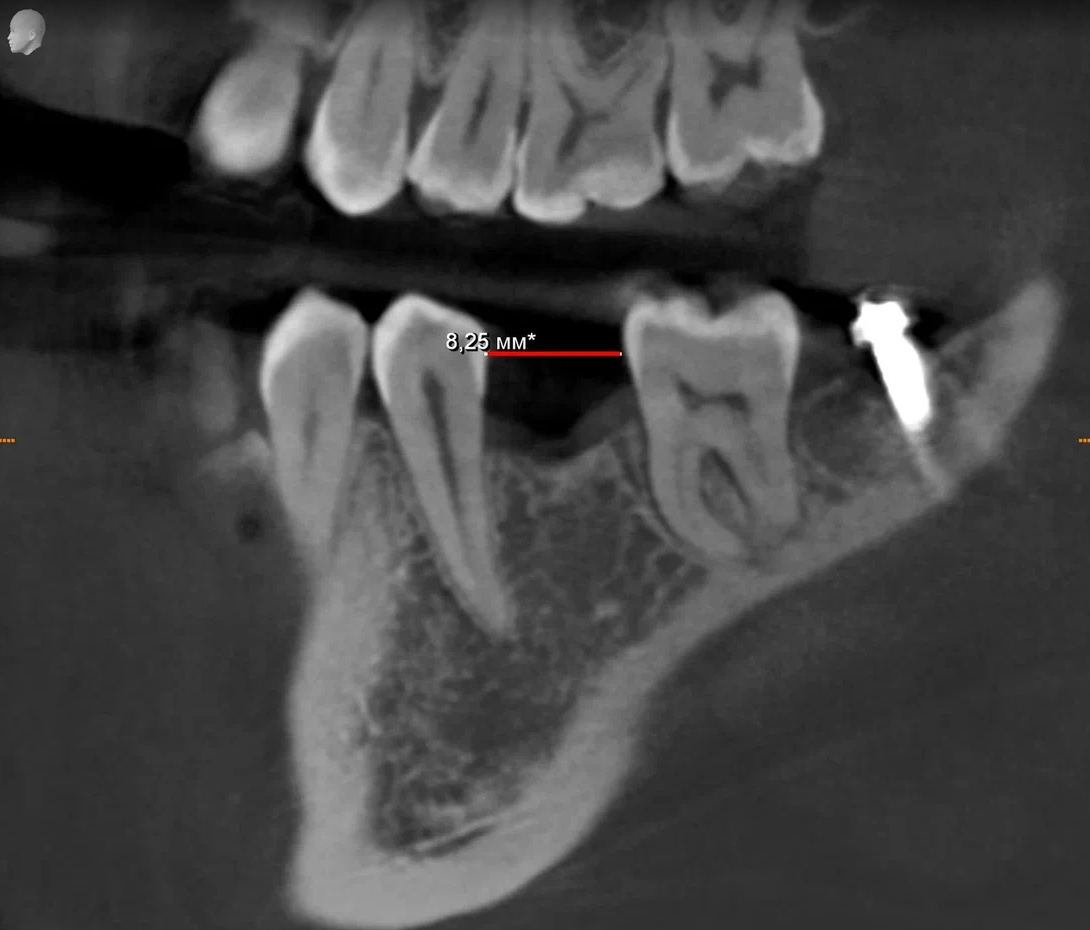

Имплант — это титановый штифт, который хирург устанавливает в кость. После операции начинается процесс заживления и адаптации тканей — он называется остеоинтеграцией.

• Используем цифровое моделирование операции и навигационные шаблоны для точной установки имплантов.